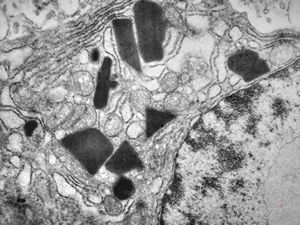

myelinoid inclusion

myelinoid inclusion in an unclassified tumor - peroxisome?

myelinoid inclusion in an unclassified tumor - peroxisomes?